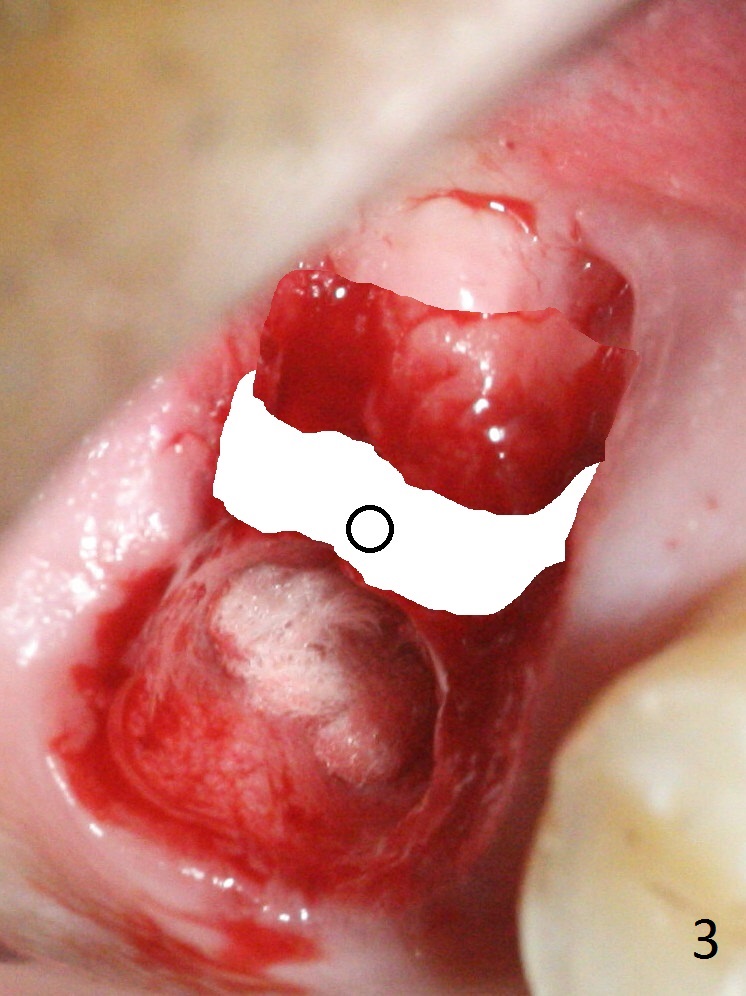

The palatal socket (Fig.1 P, packed with gauze) is intact, but implant trajectory may not be ideal. Buccal to the palatal socket are 2 pieces of the gingiva, buccal (B) and Septal (S). After the septal gingiva is pushed buccally (Fig.2 arrow), the underlying sloped septal bone is exposed (Fig.3 white area). Osteotomy is established as palatal as possible (Fig3 black circle) using DIO Sinus Master Kit, supplemented by Tatum osteotomes and DIO SM 3.8 mm tap drill for final sinus lift (Fig.4). Following further osteotomy using 4.1 and 4.5 mm taps, a 4.5x10 mm implant (Fig.6,7) with insertion torque >65 Ncm. Due to buccal bone loss, the coronal buccal threads are exposed 1-2 mm, which is covered by combination of allograft, autogenous bone and Osteogen. Prior to implantation, PRF plug and bone graft are used for sinus lift. The septal gingiva now is approximately 1-2 mm coronal to the implant plateau (Fig.5 S). The most coronal buccal gingival defect is covered by 3 pieces of PRF membrane (Fig.5 M) against a 6.8x5.5(6) mm abutment (A). Finally the socket is protected by periodontal dressing (Fig.8).